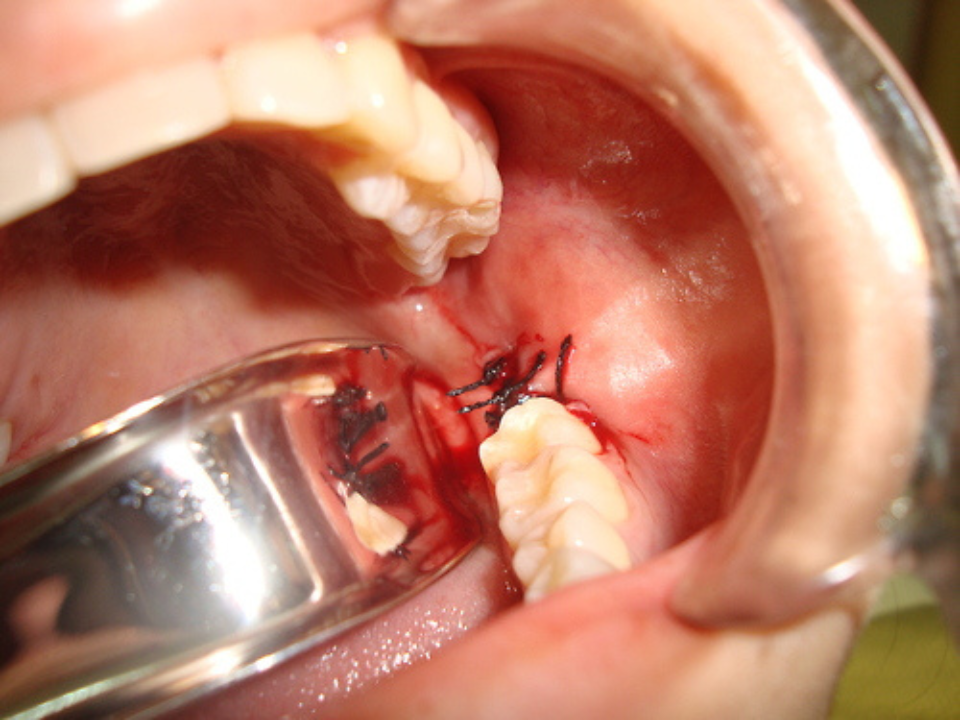

A Cirurgia Bucal é uma especialidade da odontologia voltada para a realização de procedimentos cirúrgicos na cavidade oral. Entre os mais comuns estão a extração de dentes (inclusive sisos), remoção de cistos, biópsias, frenectomias e tratamento de lesões nos tecidos bucais.

Essas cirurgias são indicadas tanto para resolver problemas funcionais quanto estéticos, promovendo saúde, alívio de dores e prevenção de complicações futuras. Realizadas com técnicas seguras e anestesia local, as cirurgias bucais são fundamentais em muitos tratamentos odontológicos, sendo frequentemente o primeiro passo para reabilitações com implantes ou próteses dentárias.

Se você precisa remover dentes, tratar cistos ou corrigir problemas mais complexos, as cirurgias bucais são a solução. Conte com nossa equipe especializada para um cuidado cuidadoso e preciso.